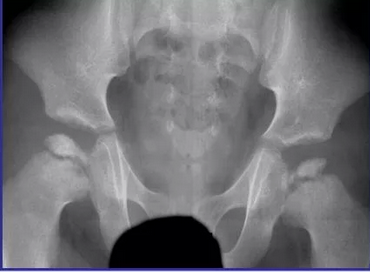

В случае перелома шейки бедра компания МосРентген Центр госпитализирует в Склиф для эндопротезирования.